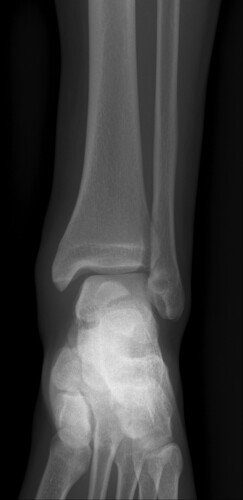

Eu sou o Luan de Couet Marafon, zagueiro do Caxias Sub 17 e sofri uma fratura grave no tornozelo esquerdo durante um jogo e preciso fazer uma cirurgia. Estou fazendo essa vaquinha para ajudar a cobrir o valor do procedimento cirúrgico, exames, fisioterapia e demais despesas. Quem puder ajudar com qualquer valor ou compartilhar, ficarei grato!